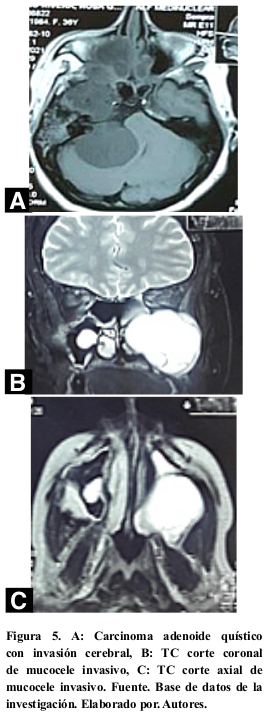

El estudio histopatológico reportó tumores benignos en el 72,41% (21; 29) de los casos, siendo el más frecuente el AFNJ 68,97% (20; 29), tumores cerebrales invasivos 6,90% (2; 29) (Figura 4 y 5); seguido de los tumores malignos con el 20,69% (6; 29) siendo el carcinoma adenoideo quístico el más frecuente. Tabla 1 y 2.

Las masas de origen cerebral que invaden senos paranasales se asocian a un gran tamaño24; según Ostrom et al.25, los tumores cerebrales primarios reportados en un 36,8% fueron meningiomas; 30,9% tumores malignos y 17,5% tumores de pituitaria y ducto craneofaringeo. Hou W, et al.26, reportó que las localizaciones frecuentes estuvieron en la convexidad cerebral; el 59,3% en área parasagital circundante; el 13,5% área al seno transverso y al seno sigmoideo. Panchani27, indicó que hasta el 2,0% de los tumores hipofisarios tienen una extensión infraselar; siendo excepcional la extensión a cavidad nasal y senos; en esta casuística correspondieron a un meningioma y adenoma hipofisario.